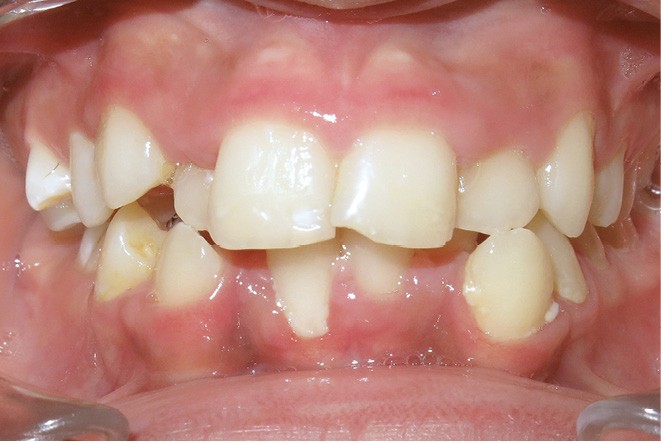

Le niveau d’hygiène est alarmant, car le rituel du brossage des dents n’est pas instauré dans la famille. Des caries se sont développées sur les dents temporaires et en ont imposé l’extraction. Les molaires permanentes ont dérivé mésialement, réduisant l’espace disponible sur l’arcade.

En denture adulte, la DDM est majeure avec un déficit de place estimé de 13 mm à la mandibule. Les lésions carieuses ont aussi touché les premières molaires permanentes maxillaires. La 26 a été avulsée et la 27 a pris sa place. Côté controlatéral, la 16 est fortement délabrée, rendant impossible sa conservation. Les molaires ayant plus mésialé à l’arcade mandibulaire, les rapports occlusaux sont de classe III. Les incisives sont versées vers l’avant, mais nous pouvons considérer qu‘il s’agit d’une biproalvéolie ethnique. Du point de vue squelettique, le patient présente une classe II squelettique par rétromandibulie sur un schéma facial hyperdivergent (fig. 1a-j).